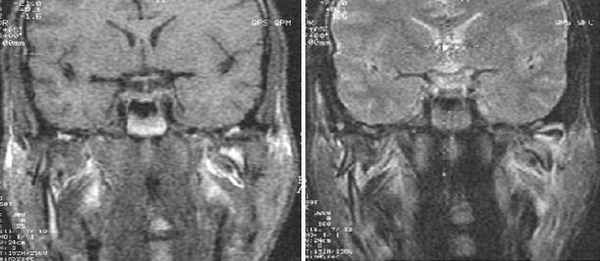

(Слева) На косой сагиттальной МРТ (Т2 ВИ) левого ВНЧС с закрытым ртом визуализируются задний пучок и переходная зона диска, нормально расположенные относительно мыщелка.

(Справа) На косой сагиттальной МРТ (Т2 ВИ) с открытым ртом у этого же пациента определяется ограничение трансляции мыщелка. Отсутствует трансляция диска по заднему скату суставною возвышения. Задний пучок диска занимает наиболее высокое положение в суставной ямке. Область соединения переходной зоны и переднею пучка находится между мыщелком и суставным возвышением.